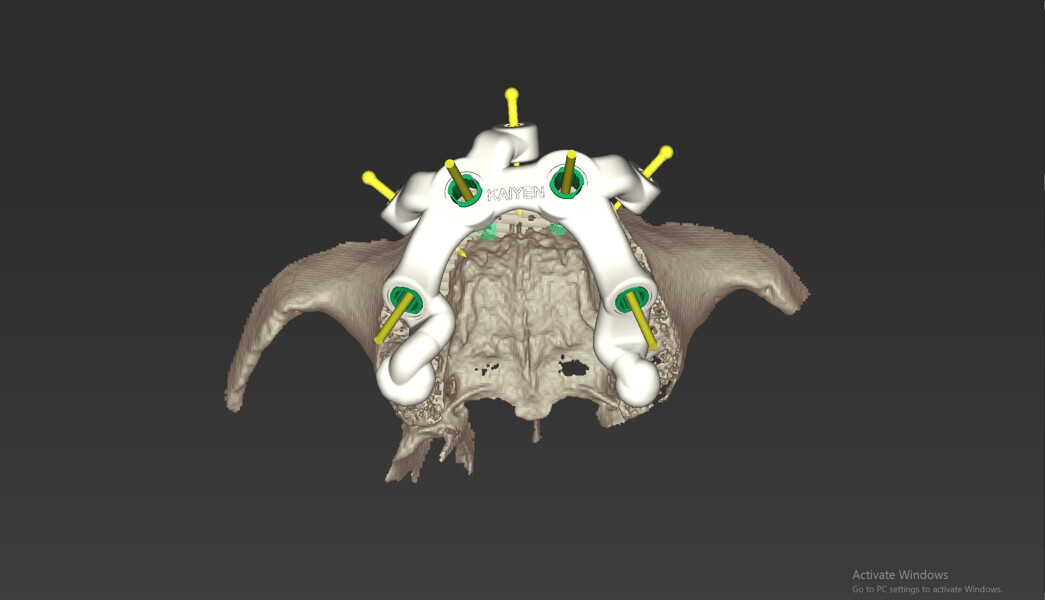

Compromised maxillary dentition treated with Straumann Pro Arch and a digital workflow